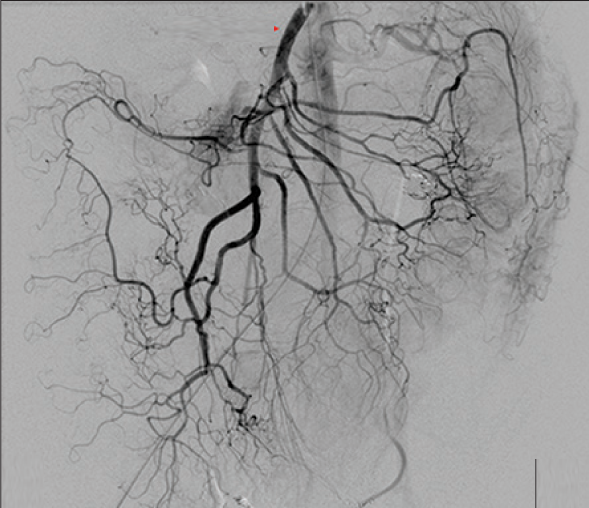

抗凝剂:肝素 溶栓药物:尿激酶、阿替普酶 ![]() 7 名患者 在动脉内内给予托拉唑啉、肝素、尿激酶进行血管造影操作 2 名患者出现出血性诱因情况 外科治疗 ![]() 回顾性分析(2002 年至 2008 年) 34 名患者(年龄 7 至 92 岁),36 例刺激性肠造影检查 全身性使用肝素 动脉内给药的血管扩张剂 11 名患者(占 31%)出现出血情况的检测结果。 10 栓塞治疗 病例1 消化道大出血 血压 70/40mmGg

病例三 77岁女性复发性胃肠道出血,需要多次输血并入住ICU。(d)栓塞后无外渗。箭头指向栓塞部位。

激发试验药物剂量和结果![]() 、、 ![]() 本文是一篇发表在《Journal of Gastrointestinal Surgery》上的研究通讯文章,题目为“Provocative Mesenteric Angiography: Outcomes and Standardized Protocol for Management of Recurrent Lower Gastrointestinal Hemorrhage”。该研究旨在评估激发肠系膜血管造影(PMA)在复发性下消化道出血中的有效性和并发症,并探讨是否可以在多学科环境中建立一种技术操作规程。 研究方法研究团队回顾了其机构在过去12年(2008年至2020年)期间进行的下消化道出血肠系膜血管造影的数据,基于CPT代码75726筛选出符合条件的病例。进一步分析了其中的PMA病例,排除了医源性、手术性或创伤性原因引起的下消化道出血。挑衅性造影的诱导方案包括使用硝酸甘油扩张血管、肝素抗凝以及组织纤溶酶原激活剂(tPA)溶解血栓。 研究结果在12年的研究期间,共进行了36例PMA。其中16例(44%)为阳性结果,20例(56%)为阴性结果。阳性组和阴性组之间在患者人口统计学特征、既往下消化道出血史、先前住院次数、Charlson合并症指数评分或术前血红蛋白水平方面没有显著差异。所有阳性病例均接受了栓塞治疗,且无出血并发症,无再出血事件,也未出现缺血性肠病后遗症。尽管有两名患者(12.5%)在30天内因复发性出血再次入院,但这一比例显著低于在阴性研究中再出血的60%。 结论本研究是迄今为止最大的文献,表明PMA在适当选择的患者中能够成功诱发和治疗下消化道出血。此外,该程序是安全的,即使使用较高剂量的tPA,也没有发生出血或缺血性肠病并发症。研究机构采用了一种修改后的现有社会指南协议,将PMA纳入下消化道出血的管理流程。 其他信息文章还提到了一些相关的参考文献和被引用的文章,涉及早期与标准结肠镜检查、急性下消化道出血的门静脉造影预测因素和结果、隐匿性胃肠出血的挑衅性肠系膜血管造影更新等内容。这些文献提供了更多的背景信息和相关研究支持。 激发血管造影并发症 与“激发”试验直接相关的并发症